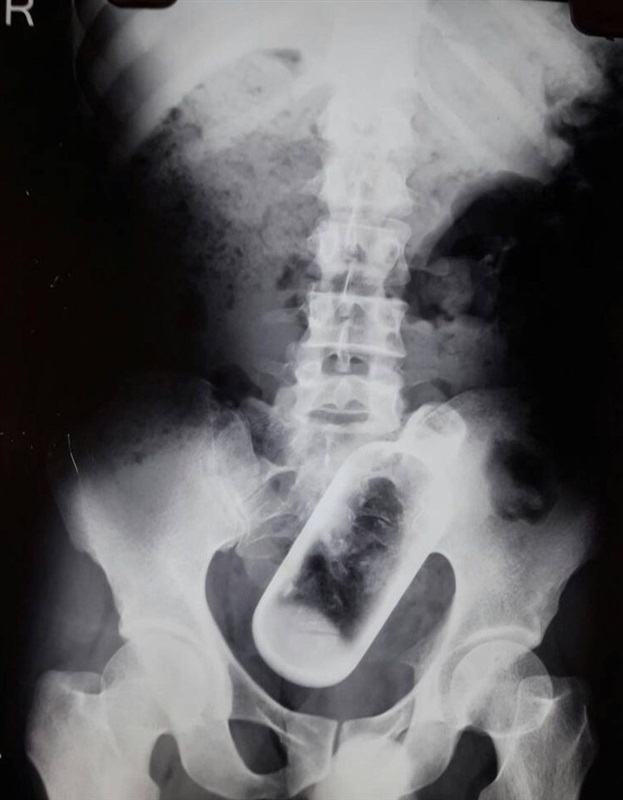

وأصيب الرجل بالصدمة عندما أدرك أن داخل معدته زجاجة طولها 16 سم، حيث فوجئ الأطباء بالزجاجة داخل جسمه بعد إجراء فحص بالأشعة السينية.

يذكر أن إزالة الزجاجة استغرقت 4 جراحين ونصف ساعة فقط في معهد مهراجا أجراسن للبحوث الطبية والتعليمية في الهند.